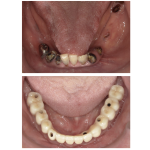

こちらは二次手術直前の状態です。

黄色のラインは歯ぐきのラインとなります。手前の歯の周りにも歯ぐきはほとんどない状況となっておりました。

また、青のラインは頬小帯(きょうしょうたい)というスジ状の繊維となり、歯のすぐそばまで存在していることで歯ブラシが当たると痛みを伴う状況が続いておりました。そのため汚れが管理しづらく、虫歯にもなっていたため、虫歯治療のために仮歯となっております。

丸印のところにはインプラント体が埋まっているのですが、二次手術時にその直上の歯ぐきに穴を開けるだけのパンチングといいう方法をとってしまうと、インプラントの歯の周りにも歯ぐきがない状態となってしまう状況でありました。